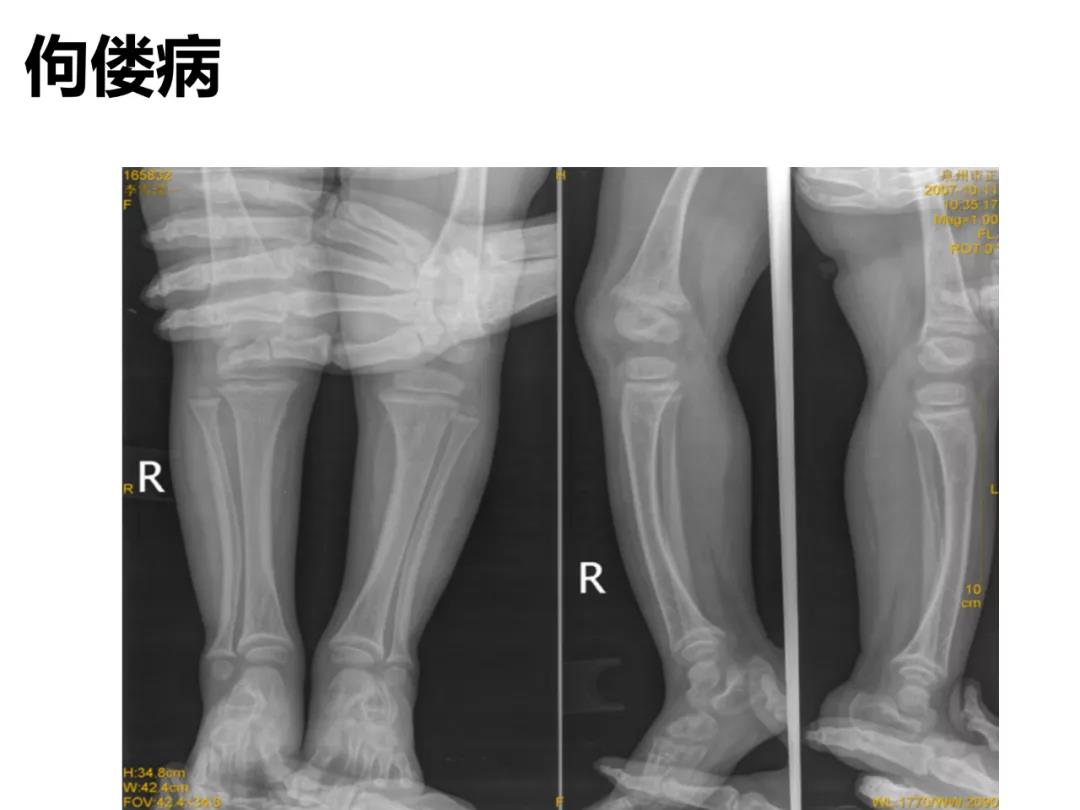

小儿骨科X线片汇总,临床读片宝典!